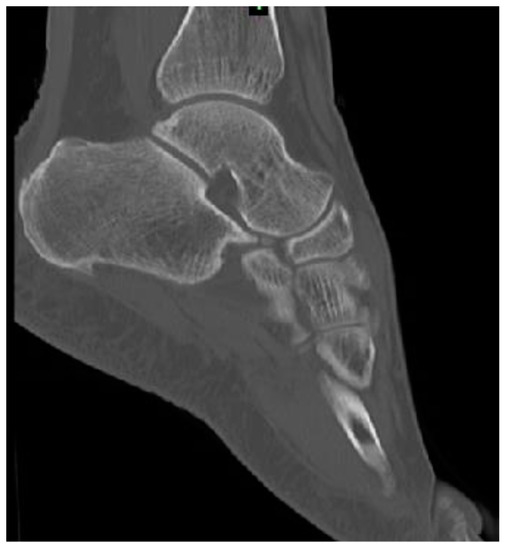

2. Numerical Bone Modelling